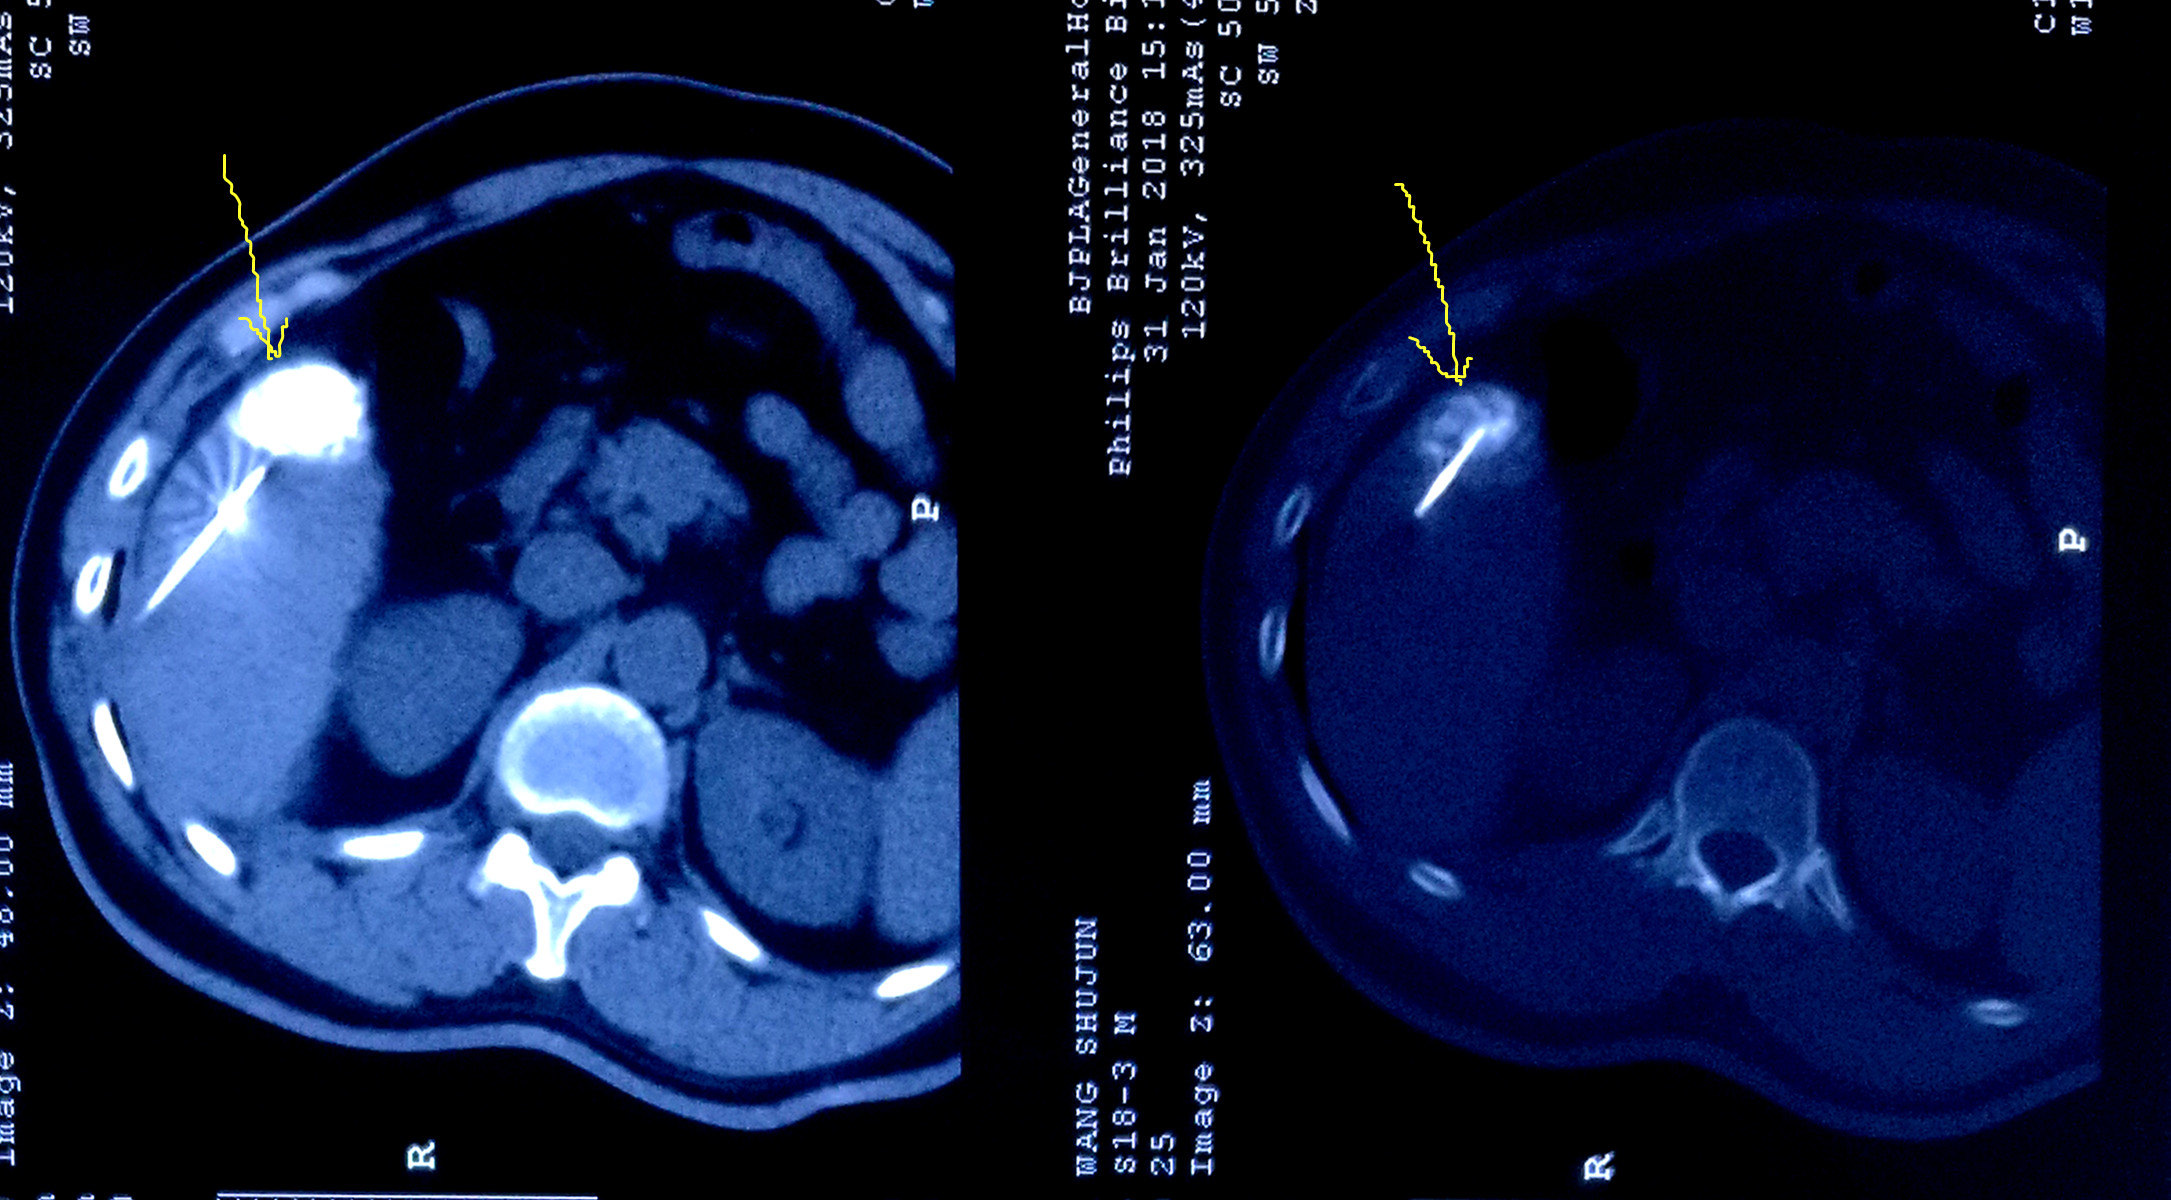

术前必须搞明白,立马做DSA,果真发现另外两个微小病灶,一个在8段,一个在5段,随即做了TACE,将三个病灶全部栓塞。一周后在CT引导下我用射频将三个病灶全部毁损,效果很不错。

接下来的几年里密切随访,又做两次栓塞和射频,目前已三年,未出现复发和转移!